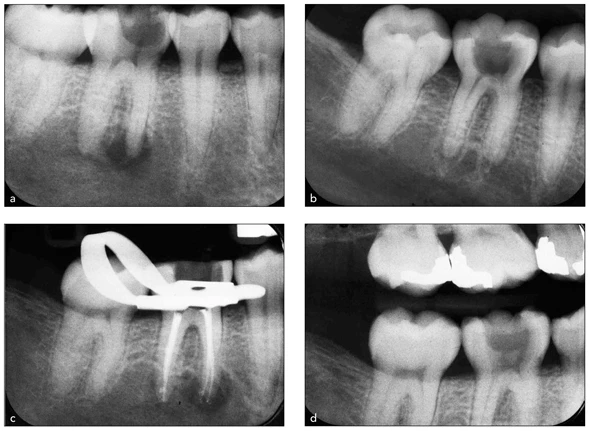

Bước đầu tiên trong việc mở lối vào tủy là sử dụng tất cả các phương tiện chẩn đoán cần thiết để nắm rõ giải phẫu buồng tủy trong từng trường hợp cụ thể. Chẩn đoán bằng X quang rất hữu ích để thấy được kích thước và vị trí của tủy răng. Đôi khi ngoài phim cận chóp còn sử dụng thêm phim cánh cắn, bởi vì nó cho thấy vị trí của tủy trong răng chính xác hơn (Hình 16-3). Lượng và độ dày của lớp men và ngà bên trên có thể được đo đạc trực tiếp trên phim cánh cắn bằng cách giữ một cây thăm dò nha chu trên phim.

Hình 16-3 Phim X quang thường quy được thực hiện trước khi mở tủy răng hàm lớn hàm dưới: ba phim cận chóp (a đến c) và một phim cánh cắn (d). Giữ một cây thăm dò nha chu trên phim cánh cắn cho phép ước lượng trực tiếp độ sâu của lối vào.